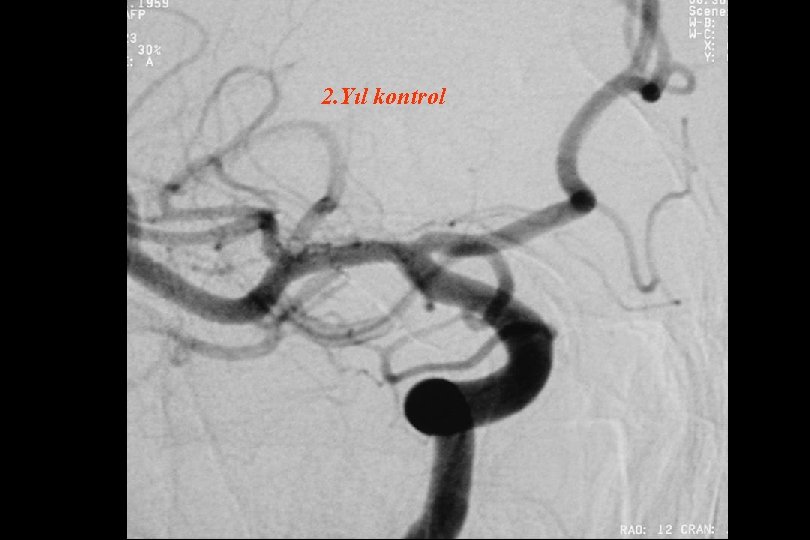

2. Yıl kontrol